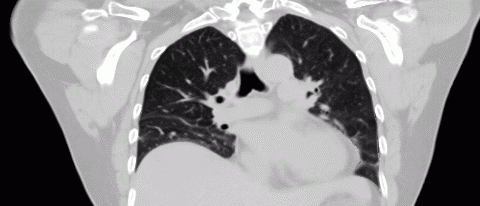

breathing

Figure 3. Example of a breathing gated image created using 5DCT.